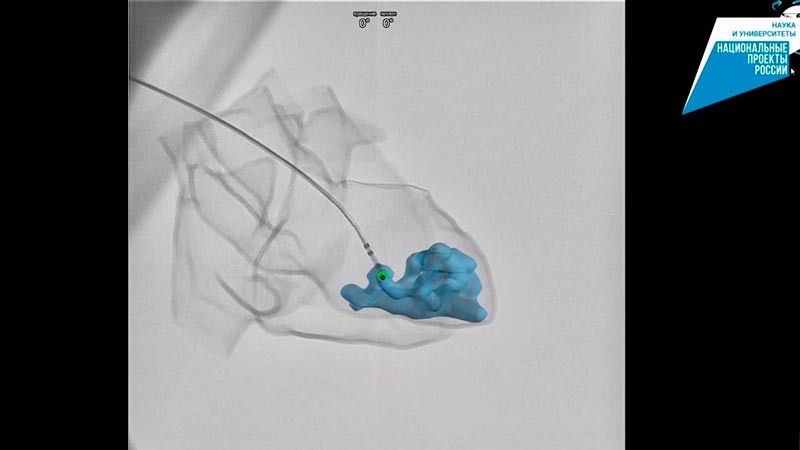

Он поможет создавать трёхмерные модели сердца и отслеживать положение хирургических инструментов во время операций.

В составе комплекса — рентгеновский аппарат с двумя излучателями, которые позволят:

✔️получать два рентгеновских изображения одновременно;

✔️запоминать параметры активации миокарда в электроанатомической модели сердца.